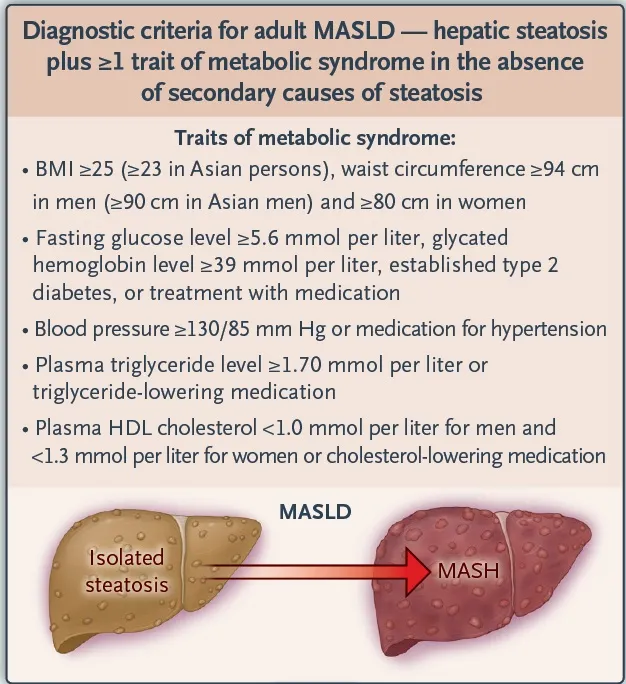

A **MASLD (metabolic dysfunction–associated steatotic liver disease)** tornou-se a principal causa de doença hepática crônica globalmente, ultrapassando hepatites virais. A transição da nomenclatura NAFLD/NASH para MASLD/MASH reforça o papel central da disfunção metabólica (obesidade, DM2, dislipidemia, resistência insulínica) como eixo da doença. Reconhecer precocemente esses pacientes é crucial para prevenir progressão para cirrose, HCC e complicações cardiovasculares — que continuam sendo a principal causa de morte nesses pacientes.

O rastreamento sistemático deve ser incorporado ao cuidado de pacientes de risco — especialmente aqueles acompanhados por nefrologistas, que frequentemente apresentam DM2, síndrome metabólica (critérios abaixo) e DRC.